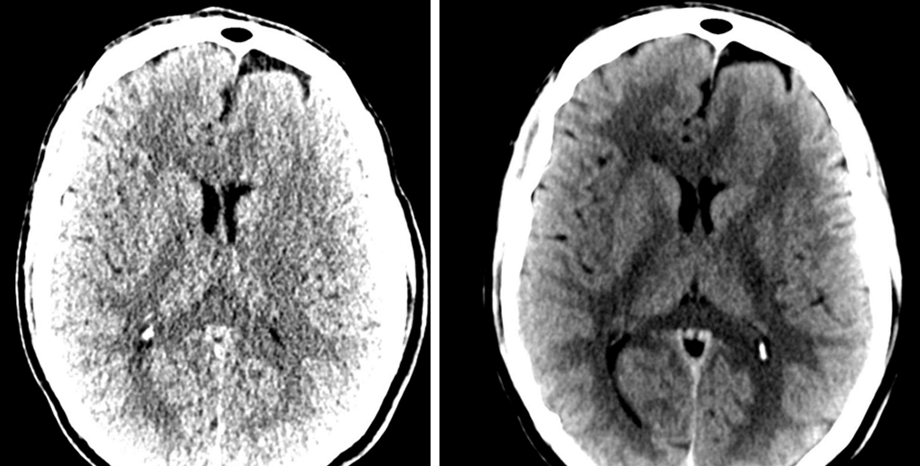

We are a labeling company

specializing in radiology, pathology, cardiology, internal medicine, and surgery. We label data and offer software development for image labeling.

MD, Radiologist, Co-Founder. US board certified Harvard trained neuroradiologist with decades of private practice experience

MD, Radiologist, and Project Manager specializing in AI applications in medical visualization, with expertise in medical data labeling